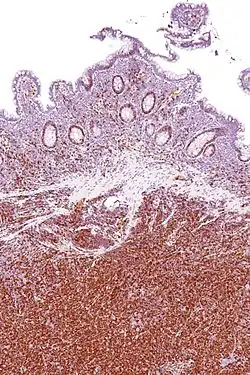

Иммуногистохимическое окрашивание на циклин D1 используется для диагностики мантийноклеточной лимфомы.